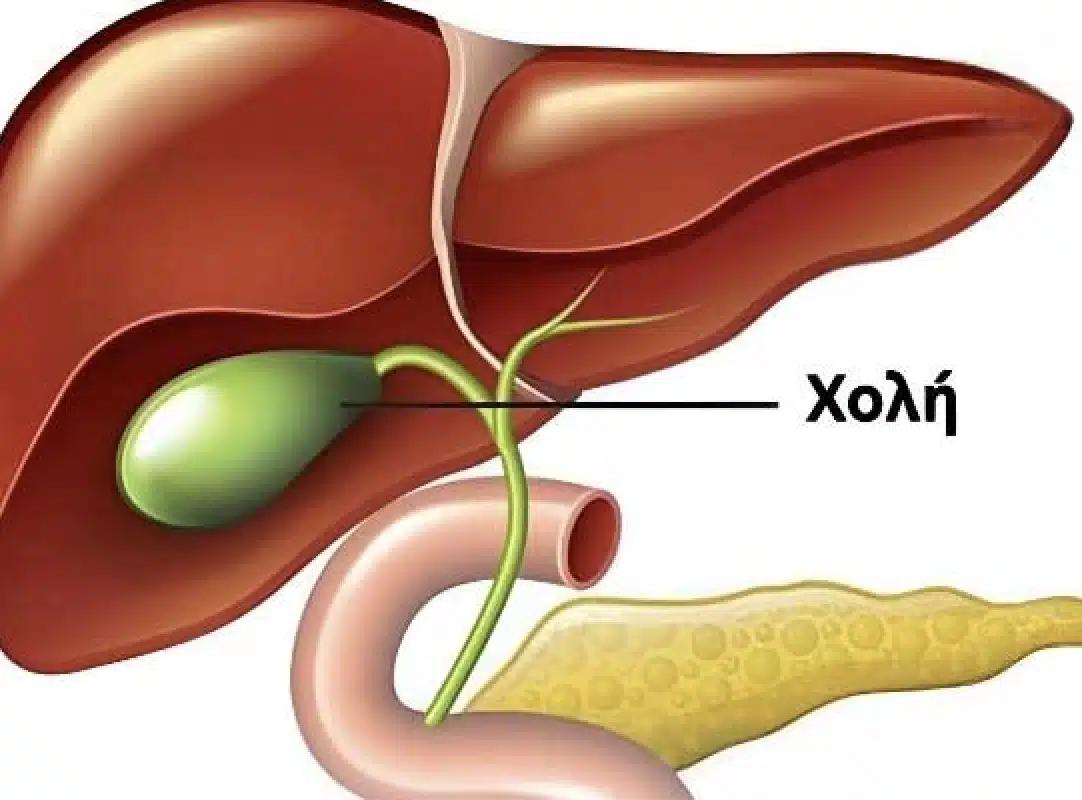

Η χοληδόχος κύστη, ένα μικρό όργανο που βρίσκεται κάτω από το ήπαρ, συνδέεται στενά με αυτό μέσω του χοληδόχου πόρου.

Η κύρια λειτουργία της είναι να αποθηκεύει τη χολή, ενεργώντας ως επιμελής φύλακας που εκτελεί σιωπηλά τον ζωτικό της ρόλο στο σώμα.

Όταν απολαμβάνουμε νόστιμο φαγητό, η χοληδόχος κύστη συστέλλεται, στέλνοντας τη χολή στο δωδεκαδάκτυλο για να βοηθήσει στη διάσπαση των λιπών. Η χολή έχει επίσης αντιβακτηριακές ιδιότητες, λειτουργώντας ως μια αόρατη αμυντική δύναμη της υγείας που διατηρεί την υγεία του πεπτικού συστήματος.